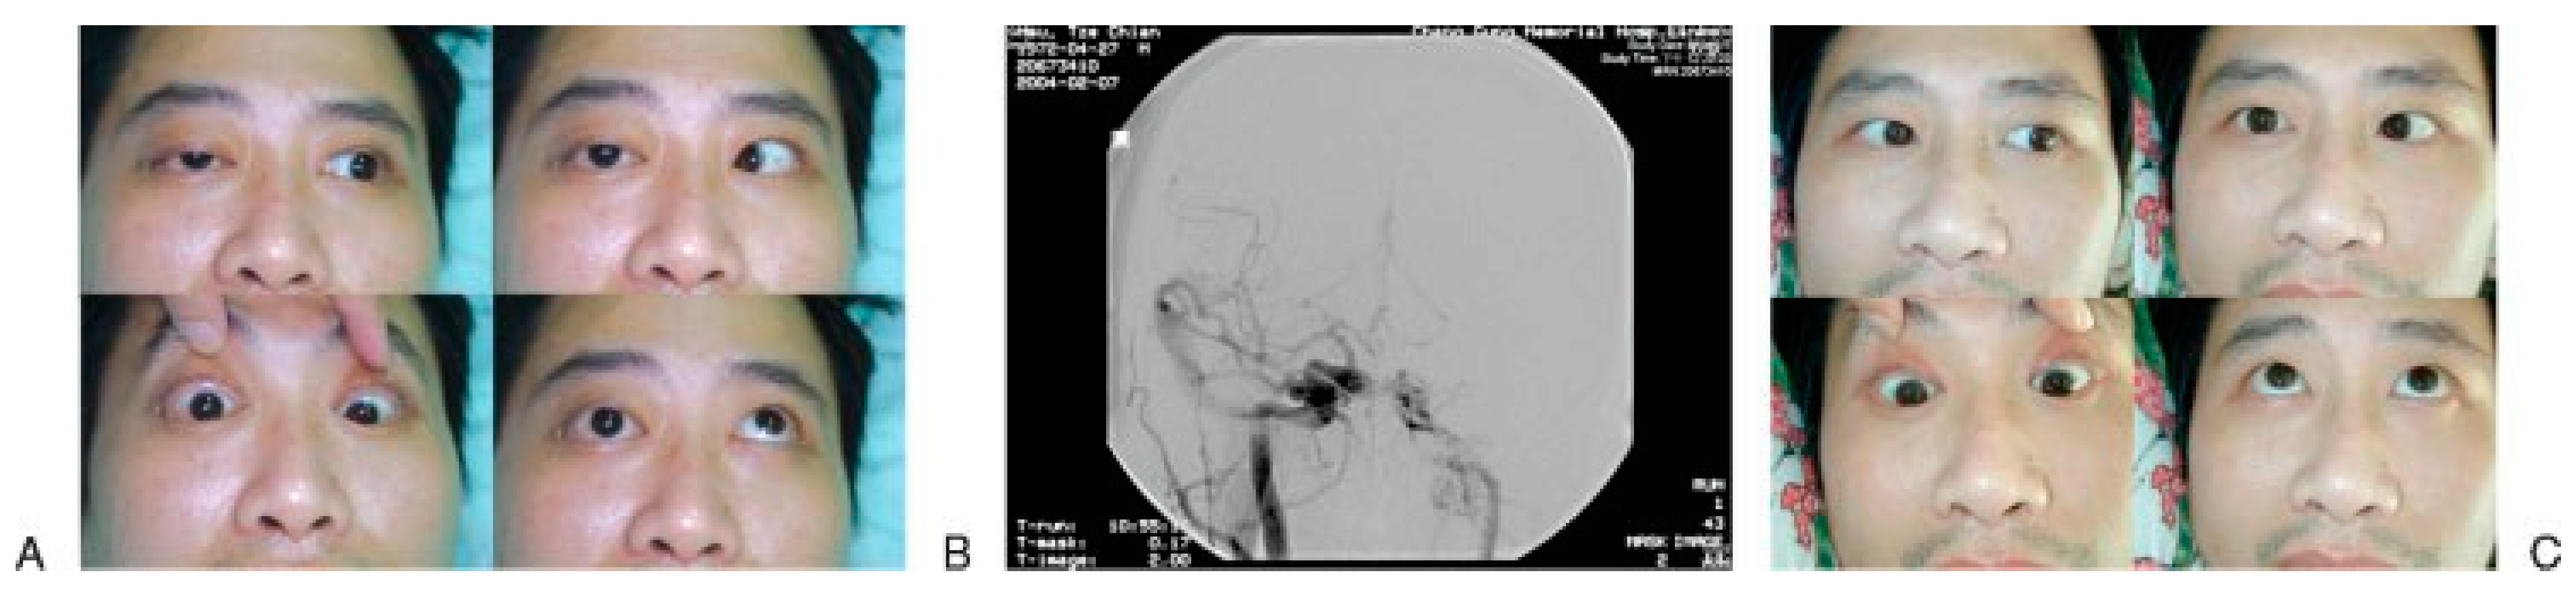

Treatment of the syndrome depends on the cause, if it can be ascertained. Patients present chemosis, pulsating exophthalmos, orbital or frontal bruit, and deterioration of vision in addition to clinical finding compatible with SOFS; traumatic CCSF [26,32] should be highly suspected as a cause of SOFS. Prompt carotid angiography is conducted to confirm CCSF, which can be successfully embolized with detachable balloon or coils [32,33]. The symptoms of ptosis, facial numbness, and ophthalmo- plegia usually resolved progressively within few months after embolization (Figure 4).

Figure 4.

A 32-year-old male with traumatic superior orbital fissure syndrome (SOFS) caused by carotid-cavernous sinus fistula (CCSF). (A) Patient presented the symptoms of SOFS along with orbit bruit. (B) Anterior-posterior right carotid angiogram showing a large CCSF. (C) One month after embolization, the eye movements are almost back to normal, except the abducens nerve.